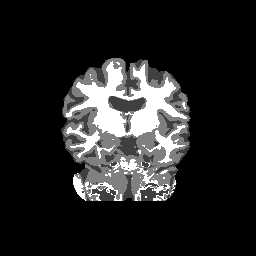

Accuracy is reported as Dice overlaps between a tool's segmentation and the Internet Brain Segmentation Repository (IBSR) manual segmentation for each of the 18 IBSR subjects. The inter-tool comparison (on the left below) shows the median Dice coefficient for each tissue class. The overlaps for FSL (from which the median values are drawn) are shown in the plot on the right.

Overlap coefficients for each tissue class are shown here for each IBSR subject. Select a subject below to see the FSL results compared to other tools.